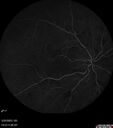

Siegrist Streaks and severe diabetic macular edema161 views56 year old female who presents four years after developing necrotizing fascitis and multiple organ failure from an infected foot from a roofing nail. Her vision was 20/100 OU. She has multiple peripheral pigment spots consistent with Siegrist streaks.Sep 19, 2023